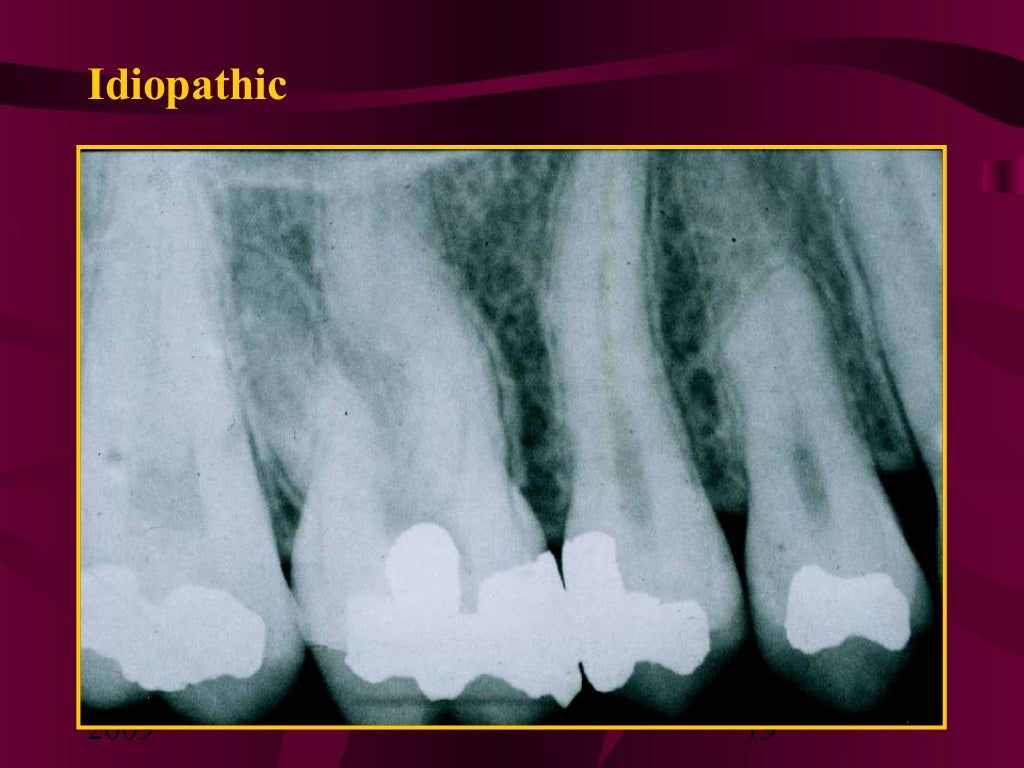

From www.slideshare.net